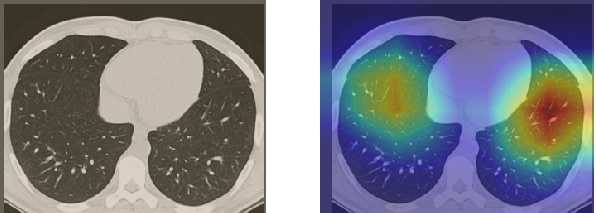

In order to make our models more transparent and provide detailed visual analysis, we present the Grad-CAM localization maps obtained by different models. We consider CT images with COVID-19 abnormalities from the test set of each dataset and highlight the important regions considered for the prediction. For the SARS-CoV-2 dataset we use the Inception V3 model. Figure 13 shows the original CT images and their localization maps. Our model is capable to detect regions that show abnormalities in the CT scans.

In a similar way, we consider classifying the test CT scans from the COVID-19 dataset by the DenseNet169 model and highlight the important regions considered for predictions. We present the original CT images and their localization maps in Figure 13. We can also see that our model is capable to detect the COVID-19 related regions as marked (small square in some images) by expert radiologists.

A wide variety of typical and atypical CT abnormalities have been reported for COVID-19 patients in various studies [58, 59]. So, we tested our models on external CT images extracted from these two publications as they feature typical findings of COVID-19 pneumonia marked by specialists. In order to make sure that not any of the extracted images are unintentionally included in our datasets, specifically the COVID19-CT dataset, we use the model trained on the SARS-CoV-2 dataset. First, the InceptionV3 model is employed to classify the extracted CT images. The model is able to correctly classify the given CT images as COVID-19. Second, in order to interpret the model’s generalization capabilities, we apply the Grad-CAM technique to visualize the regions of abnormalities that are considered. By assessing the different CT images in Figure 15, we can see that the model accurately localizes the disease-related regions. Even more interesting is the fact that the model ignores any specific marks in the images like letters and only localizes the COVID-19 related regions. These visual explanations show the success of our models to learn relevant, generic visual features related to COVID-19 and are capable to correctly classify CT images outside the datasets on which they are trained.

Figure 16 shows various CT scans where only one lung is visible. The CT scans are also extracted from the paper [58] and show different CT manifestations of COVID-19 pneumonia marked by red squares. The InceptionV3 model is capable to classify them correctly as COVID-19, although it is trained on CT scans where the entire lung is visible. Intriguingly, when applying Grad-CAM we can see that all regions of abnormalities are accurately localized. This also proves the potential of our model to detect COVID-19 abnormalities in CT images outside the dataset used for training.